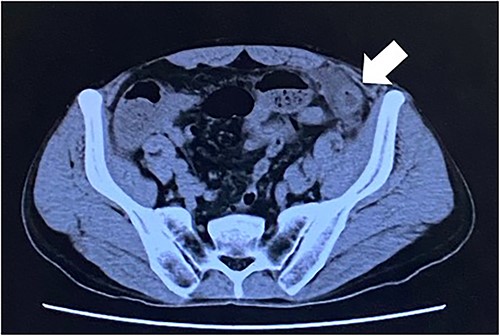

Computed tomography revealed caliber changes in the small bowel at the site of post-hernia repair in the left inguinal region (Figs 1 and 2), and the patient underwent laparoscopic surgery under general anesthesia. Intraperitoneal observation revealed that the peritoneal suture in the left inguinal region was detached, and a hole in the peritoneum had formed a hernial orifice (Fig. 4), causing SBO because of preperitoneal herniation (Fig. 3). The hernia was released, the peritoneal hole was sutured again and the surgery was completed. The postoperative course was good, and the patient was discharged from the hospital on the third postoperative day after reoperation.

The white arrow shows the small bowel incarcerating into the preperitoneal space (coronal section image).